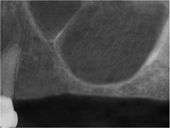

5) The membrane has been reflected from the internal aspect of the inferior portion of the sinus cavity; one can now visualize the bony floor of the sinus cavity without its lining membrane (note the triangular ridge of bone within the sinus, known as an Underwood's septum).

6) The newly formed space within the bony cavity of the sinus yet inferior to the intact membrane is grafted with human cadaver allograft bone. The floor of the sinus will now be roughly 10mm or so more superior than it was before, providing enough room to place dental implants into the edentulous site.